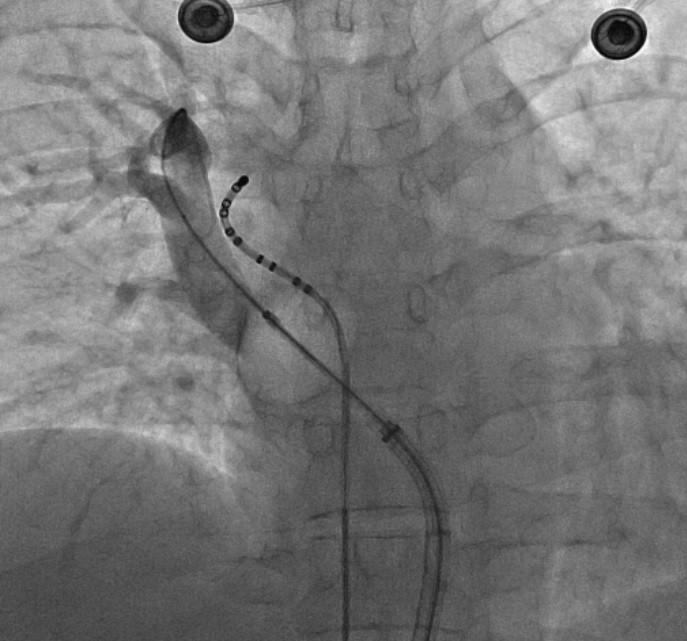

CRYO AF ablasyonu1.5 saat kadar süren, lokal anestezi altında uyutmadan yapılan ağrısız bir işlemdir. Kalbin sol kulakçığına açılan akciğer venlerinin (4 adet) giriş yerinde dondurma (-50-60 dereceye kadar soğutularak..) işlemi yapılarak gerçekleştirilir.

- Çarpıntı Tedavisi-CRYO (dondurarak) AF Ablasyonu